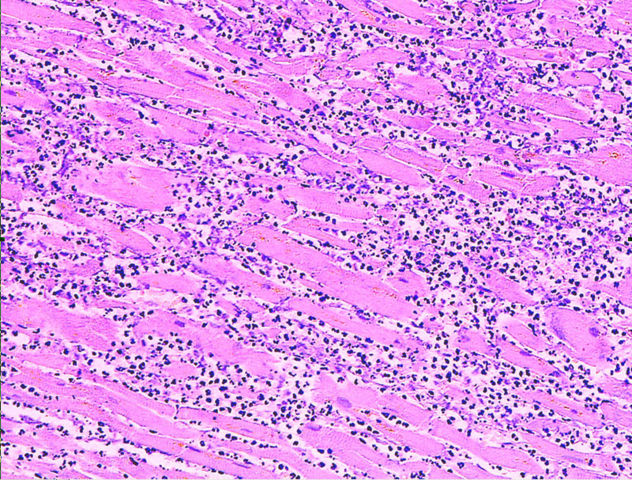

Microscopy image (magn. ca 100x, H+E stain) from autopsy specimen of myocardial infarct (7 days post-infarction)